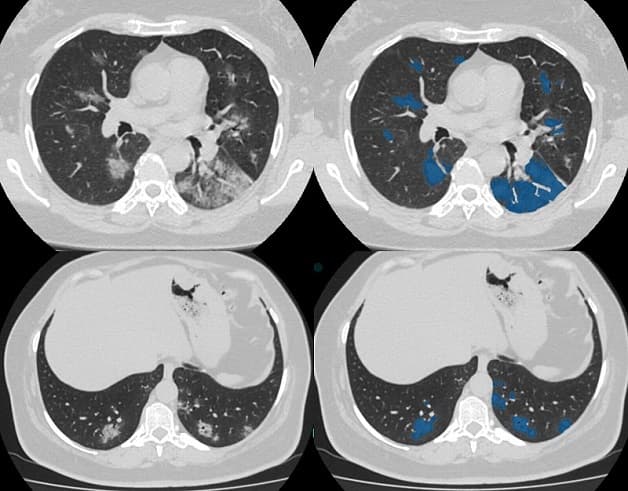

Hình ảnh minh họa phim chụp CT não